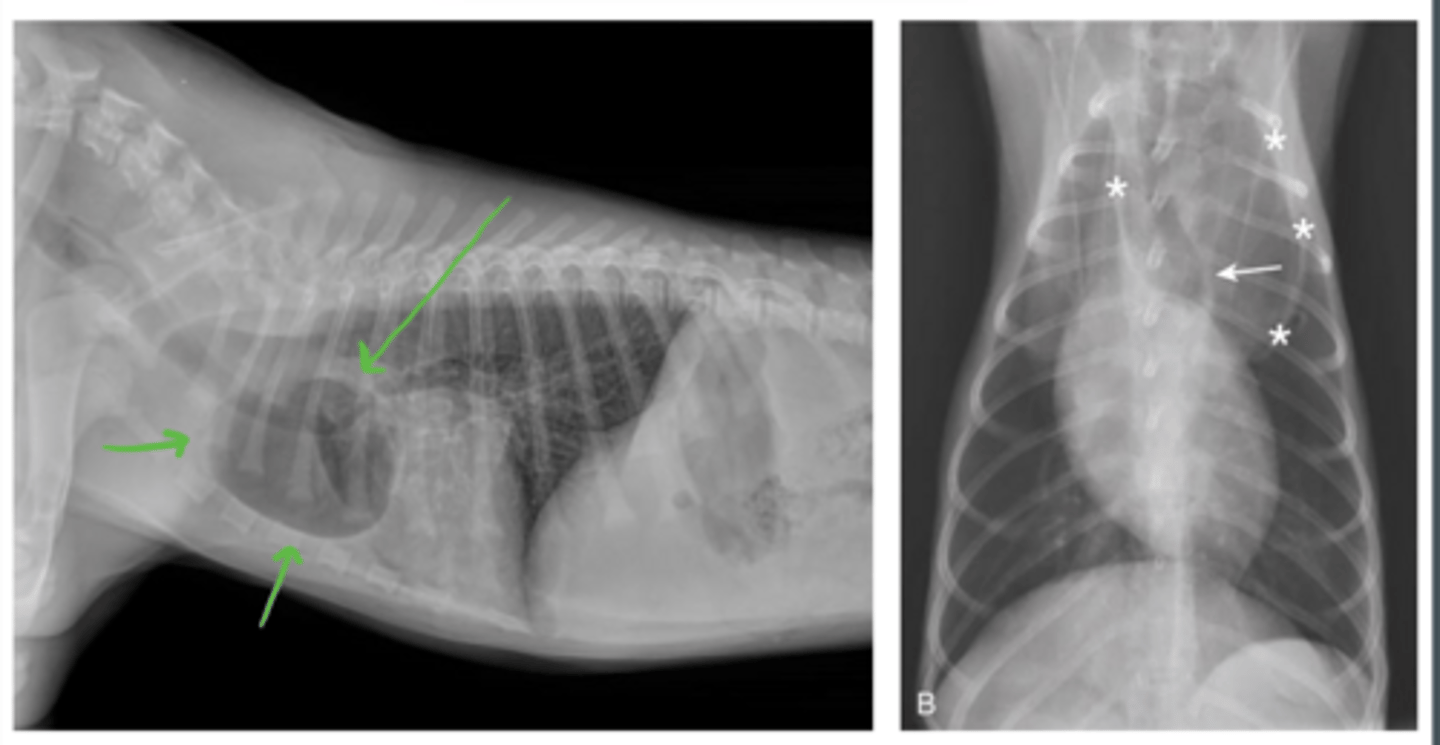

Identify?

R vascular ring anomaly